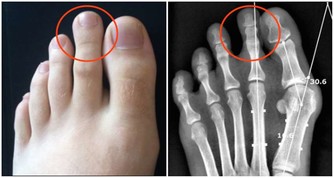

(1)痛風

痛風性關節炎發作前一定會有高尿酸血症期,但高尿酸血症不一定會發展為痛風,

從無症狀的高尿酸血症,到痛風性關節炎的首次發作需要5-10年時間;

首發症狀常表現為夜間突發第一趾蹠關節疼痛難忍、局部紅腫、皮溫增高,其發病急驟,消退也快,,可在1週左右自行緩解,痛風易反復發作,可累及多個關節,並導致關節畸形。